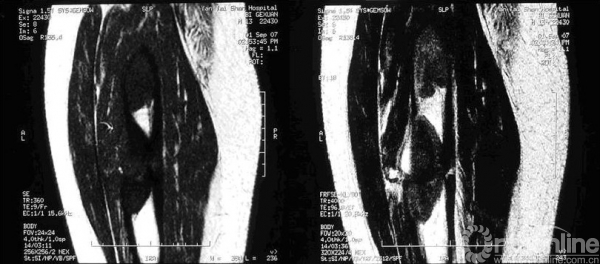

MRI检查

MRI表现比较复杂,根据病灶内所含组织的比例不同,表现也不同,多数表现为T1WI和T2WI呈不均匀的低信号,T2WI压脂像上呈中等信号(图8),病灶内有出血或积液时信号明显增高,MRI非常敏感,可早期诊断,并能清楚的确定肿瘤的范围,但对骨皮质的显示不清楚(图9)。

图8 MRI示T1和T2主要为低信号

图9 X线片显示不明显,而MRI可清楚显示